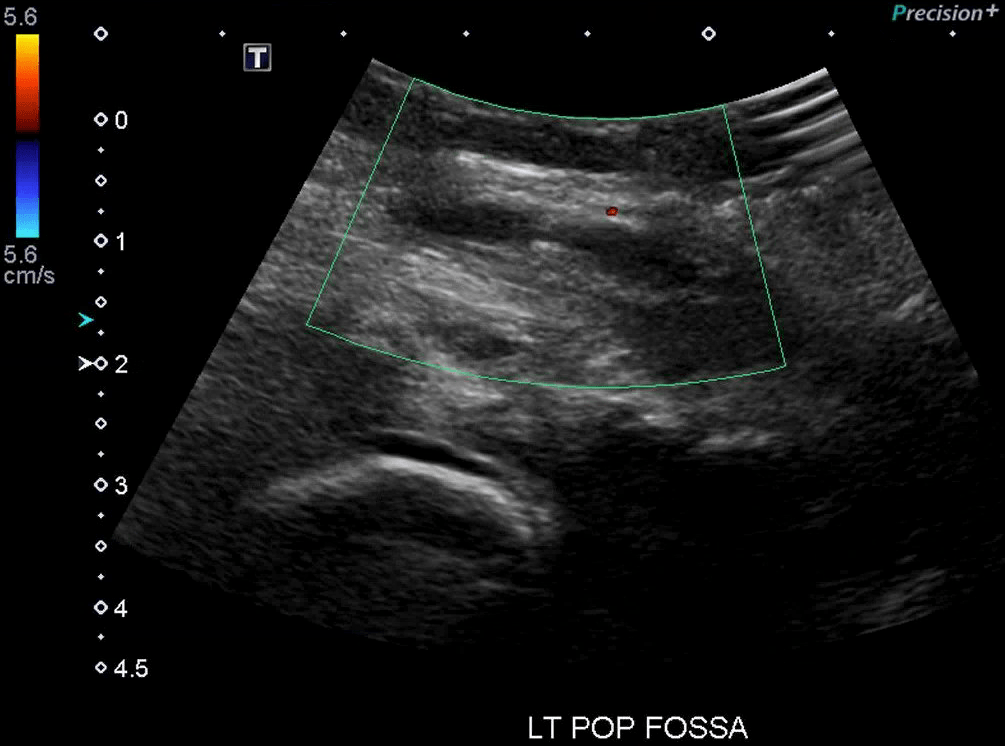

Baker’s Cysts: A Baker’s cyst forms in the popliteal fossa from an accumulation/extrusion from the synovial capsule of the knee and can be a false positive for DVT as they are anechoic and non-compressible. In the image on the left the anechoic structure within the Doppler box is a Baker’s cyst. Similar to lymph nodes they are not continuous with surrounding vasculature and have discrete rounded edges.